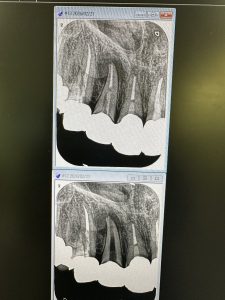

次は数年前他院で根切したが、また再発し口蓋が腫れてる

代診医から代わり、私が探り意図的穿通💪No.2

リーマ100号に相当、径0.95ミリ位

多量に排膿と出血

画像からも分かるが、根切断カット長さ、掻爬、殺菌が不十分だったのでは!

これで3回目の治療だそうだ😭